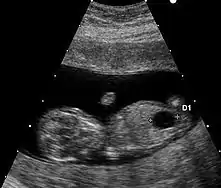

检查

在妊娠11~13+6周,测量胎儿颈项透明层厚度(NT检查)是筛查唐氏综合征等染色体异常的敏感指标。62%~80%的先天愚型胎儿可表现出颈项透明层(NT)增厚(大于3mm)。在妊娠14~16周左右,对羊水进行染色体检查可以明确判明患病与否。这种检查在一般的妇产科医院就能进行。